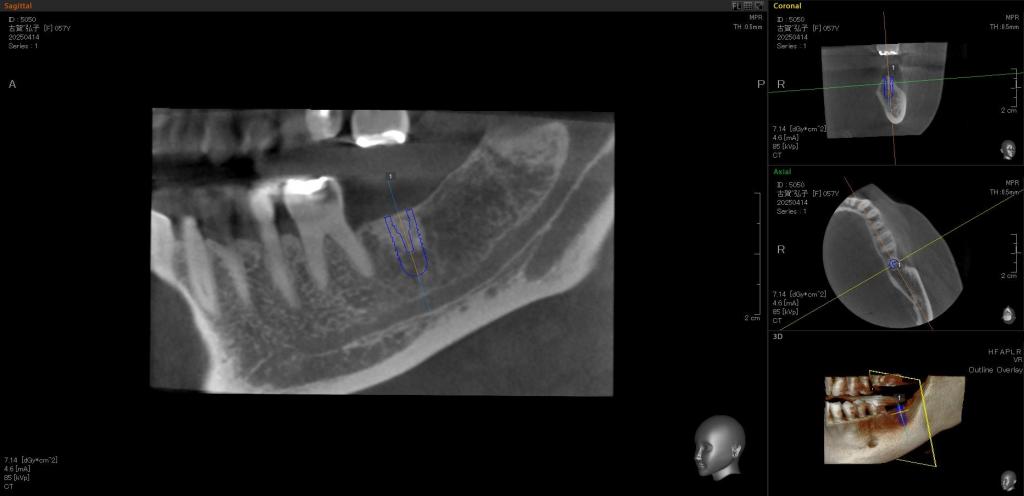

- 抜歯後、骨を作る処置を行い、患者さんと相談して「インプラント」を行うことにしました。

CTを撮影し、骨の正体を確認しました。

- インプラント埋入手術を行い、この段階でも更に「骨造成処置」を行いました。